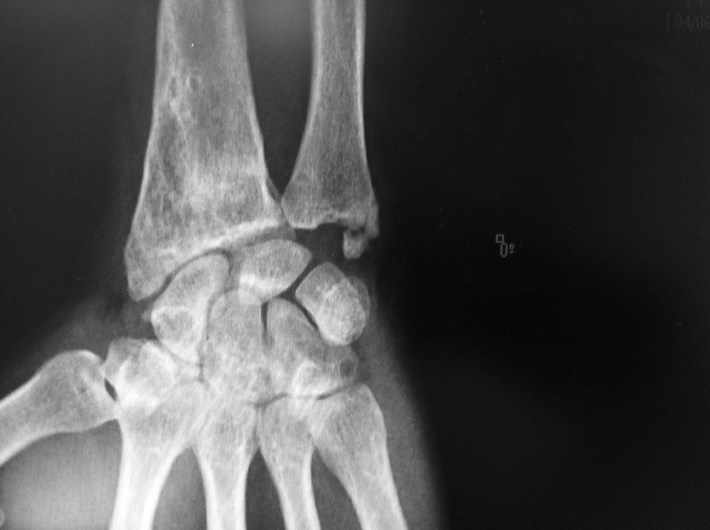

Cómo valorar radiológicamente la articulación radiocarpiana?

Estas 2 radiografías corresponden al mismo caso y están realizadas en la misma hora: Porqué en la primera, la articulación radioescafoidea aparece pinzada y el escafoides parece hundido y subluxado a dorsal?Porqué en la segunda se aprecia un mantenimineto del espacio articular radioescafoideo? La Primera es una proyección posteroanterior a 0º de elevación; la segunda es una posteroanterior a 25º de elevación ( posteroanterior con rollo de softban nuevo colocado debajo de la mano con codo sobre la mesa).

La antigua fractura del macizo estiloideo ha consolidado en flexión siendo la inclinación de la superficie articular del radio mayor a los 20º anatómicos en el plano posteroanterior. La única forma de que los rayos RX sean paralelos a la superficie articular para poder apreciar el espacio articular existente es elevar la mano sobre el eje del codo más de 20º.

Como médicos que diagnosticamos con Rx no debemos conformarnos con según qué proyecciones radiológicas se realizan . El estudio radiológico debe siempre estar orientado a diagnosticar o descartar. Las posiciones no deben ser siempre estándard. Es nuestra tarea exigir proyecciones útiles.